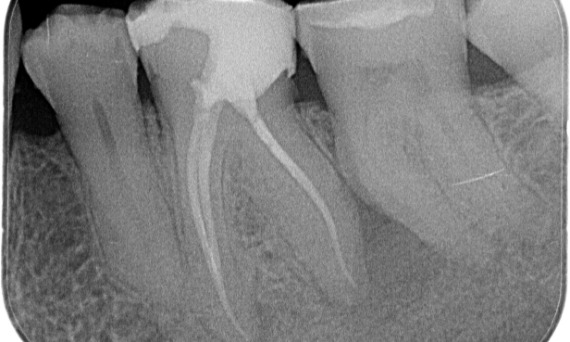

"I chose TruNatomy to be able to preserve as much dentin as possible to overcome occlusal load and increase the longevity of the tooth." - Dr. Abuelezz

Before: Upon examination, there was a caries lesion related to the lower right first molar. Radiographic examination revealed proximity of the lesion to the pulp horn and combining it with the chief complaint, a final diagnosis of chronic irreversible pulpitis was concluded.

After: Access cavity was done as conservative as possible. TruNatomy was the system of choice due to the young patient’s age. We needed to preserve dentine as much as possible to increase the tooth ability to overcome occlusal load and increase the longevity of the final restoration.

Cairo, Egypt